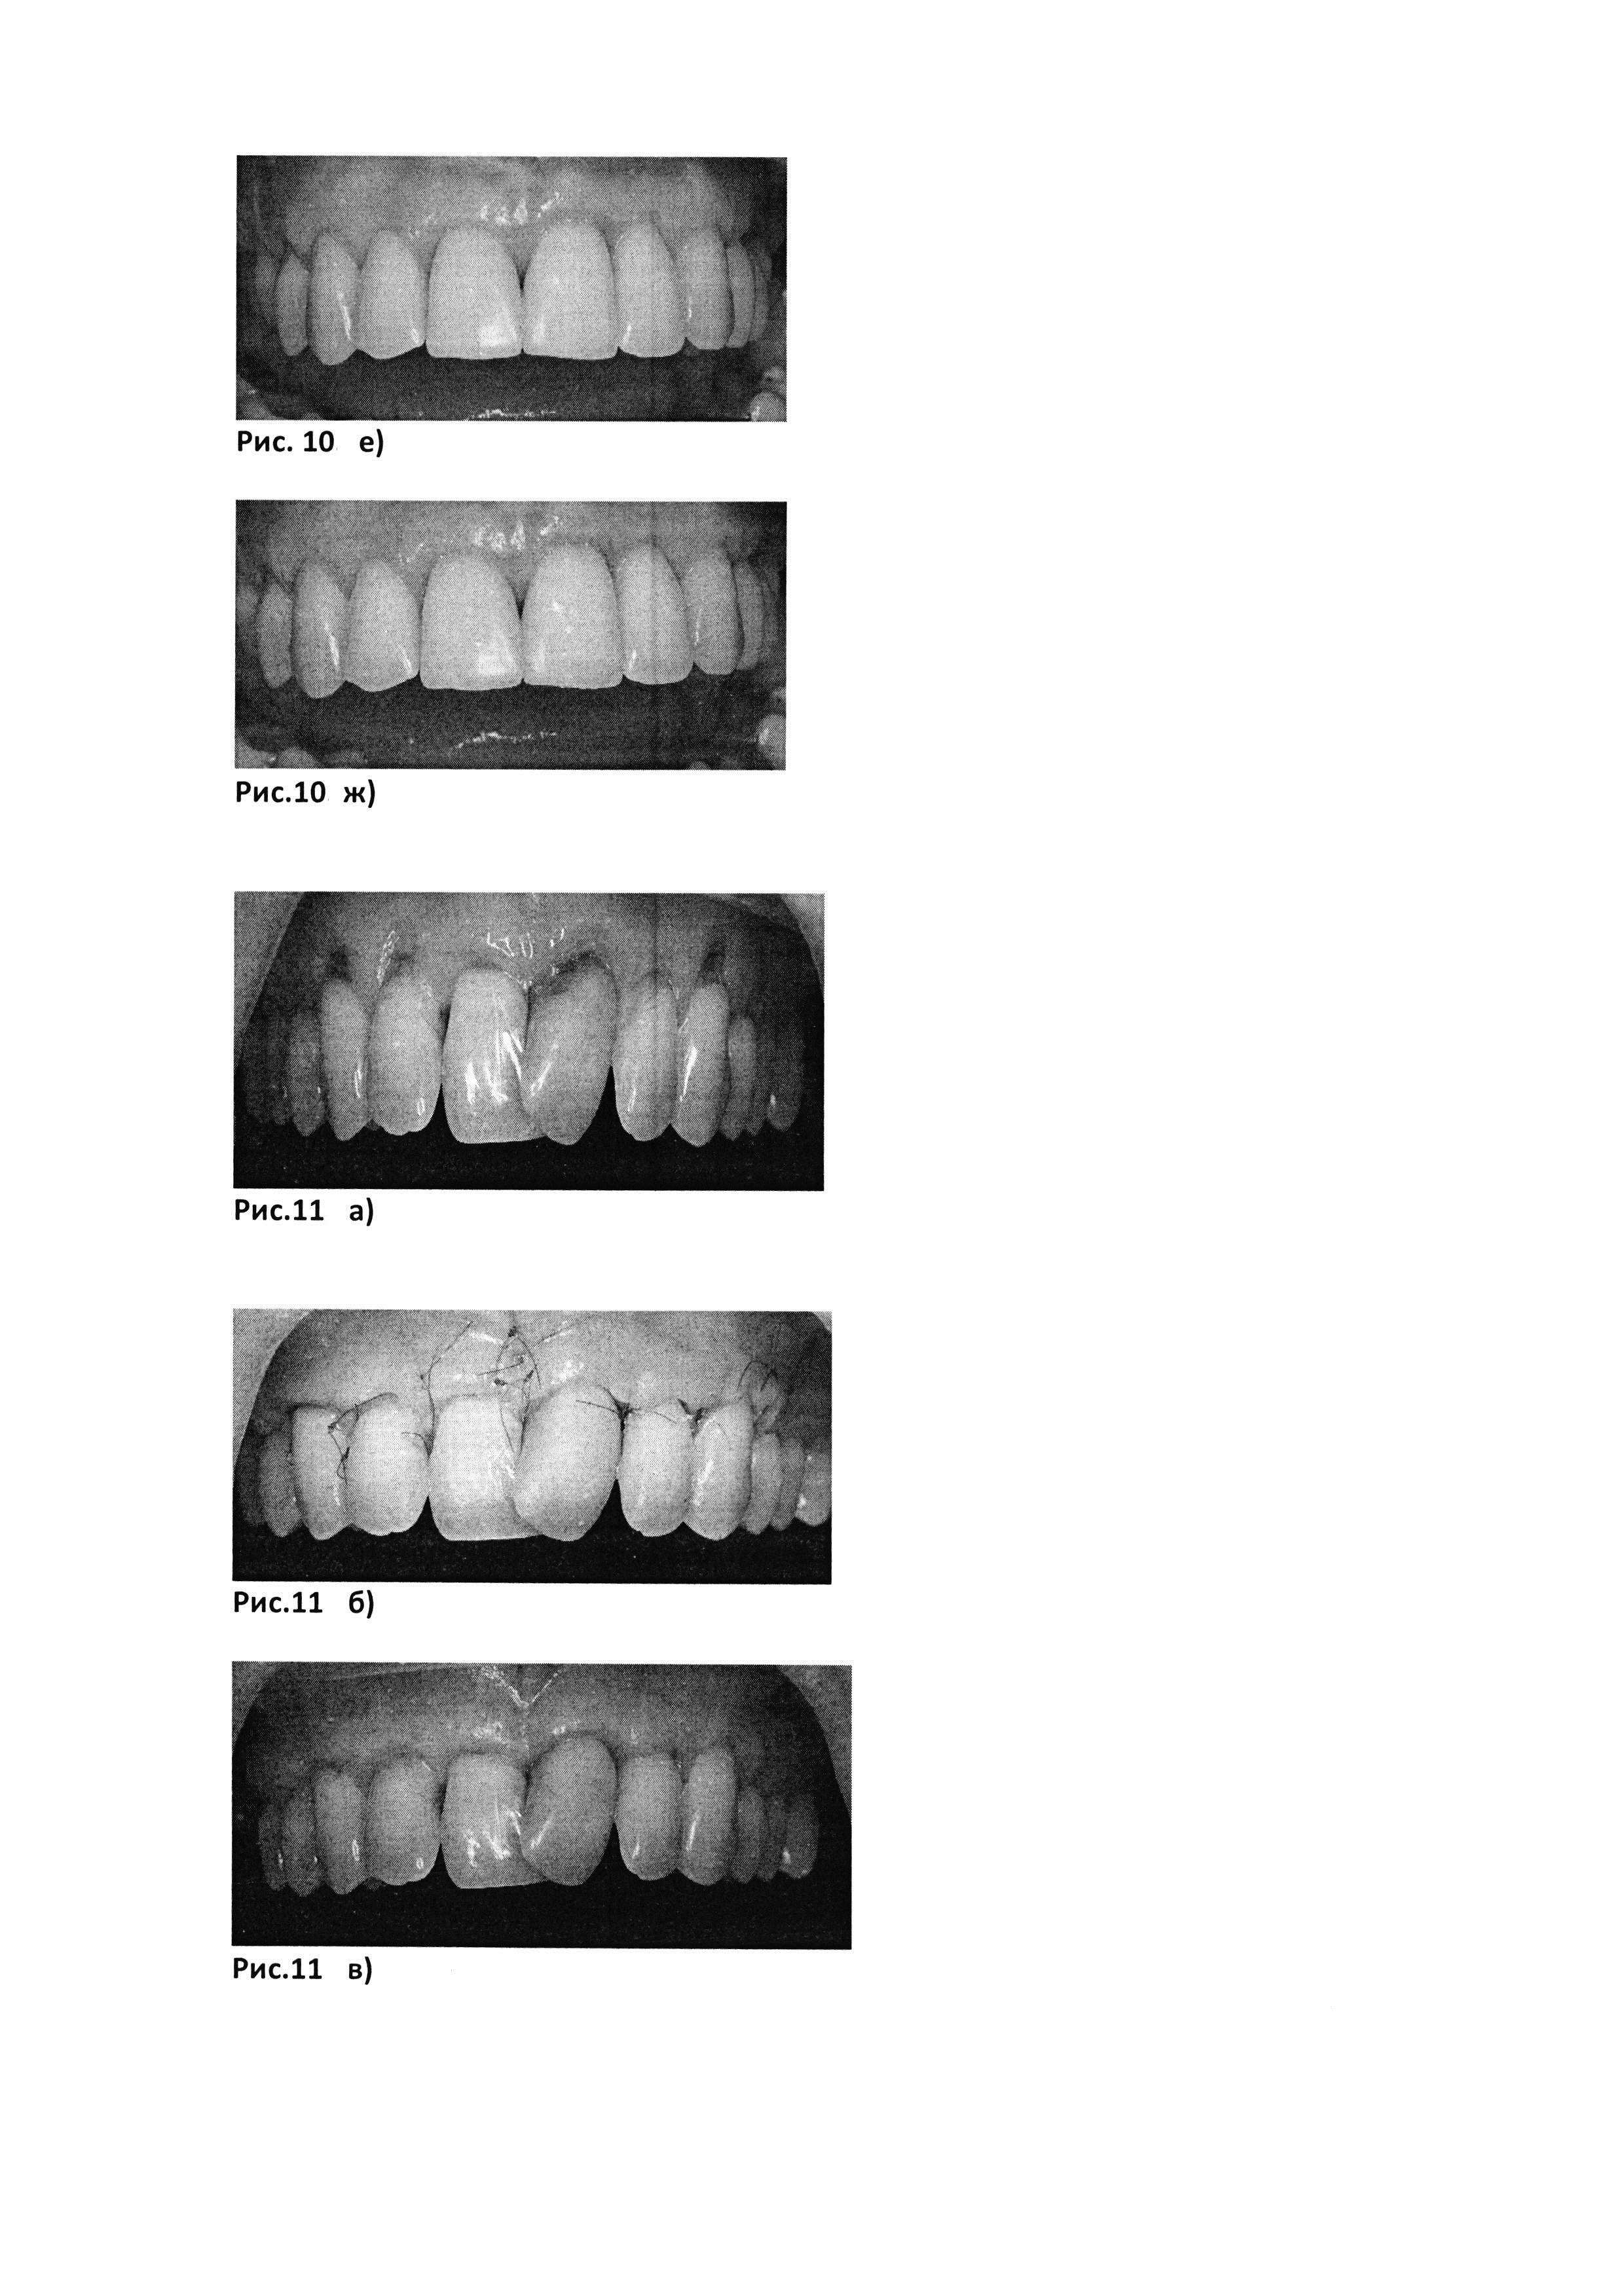

Рис. 10. е) через 3 месяца после операции

[53]

Рис. 10. ж) через 6 месяцев после операции

[54]

Рис. 11. а) до лечения

[55]

Рис. 11. б) через 12 дней после операции

[56]

Рис. 11. в) через месяц после операции

[57]

Рис. 11. г) через 3 месяца после операции

[58]

Рис. 11. д) через 6 месяцев после операции